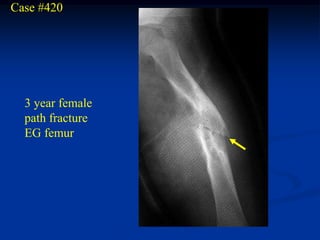

Case #420

3 year female

path fracture

EG femur

Lateral view